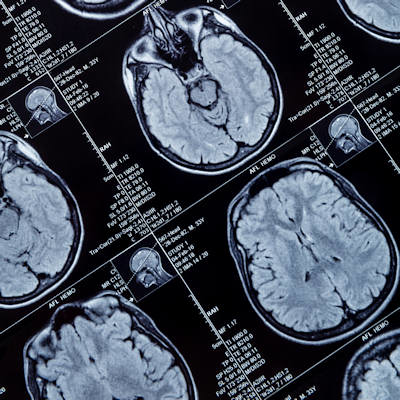

Pixyl is the developer of Pixyl.Neuro, which is CE-marked and has been cleared as a Class IIa medical device by the U.S. Food and Drug Administration (FDA). Pixyl.Neuro enables the early detection of neuroinflammatory and neurodegenerative conditions, including Alzheimer’s disease.

Caerus Medical’s technology, LumbarMR, uses AI to detect lumbar disorders (such as disc herniation, stenosis, and spondylolisthes) on MRI scans, supporting radiologists and physicians in improving the diagnosis.